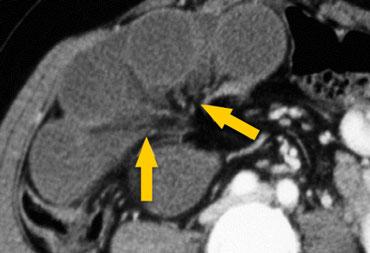

Tắc ruột dạng quai kín với các quai ruột giãn xếp theo hình nan hoa. Có dày thành ruột và phù nề mạc treo gợi ý thiếu máu cục bộ

Một hình ảnh quan trọng khác của tắc ruột dạng quai kín là các quai ruột non giãn xếp theo hình nan hoa với các mạch máu mạc treo hội tụ về một điểm trung tâm.

Hình ảnh này hầu như luôn do xoắn ruột non gây ra.

Các dấu hiệu thiếu máu cục bộ trong tắc ruột dạng quai kín tương tự như ở bệnh nhân thiếu máu mạc treo do các nguyên nhân khác:

- dày thành ruột

- phù nề mạc treo

- cổ trướng

- sự ngấm thuốc của thành ruột trong thiếu máu cục bộ có thể bình thường, tăng hoặc giảm.